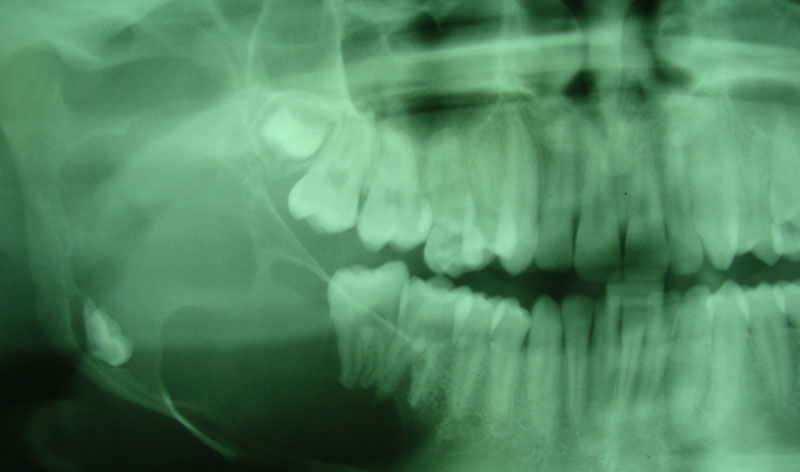

Son injertos del propio paciente extraídos del mentón o rama ascendente, destinados a aumentar la anchura del hueso indicados en maxilares con achura inferior a los dos milímetros.

Se deben fijar siempre con tornillos de 1.2 o 1.6 mm de osteosíntesis.

Terminada la reconstrucción ósea, es necesario esperar de 3 a 6 meses para la colocación de los implantes